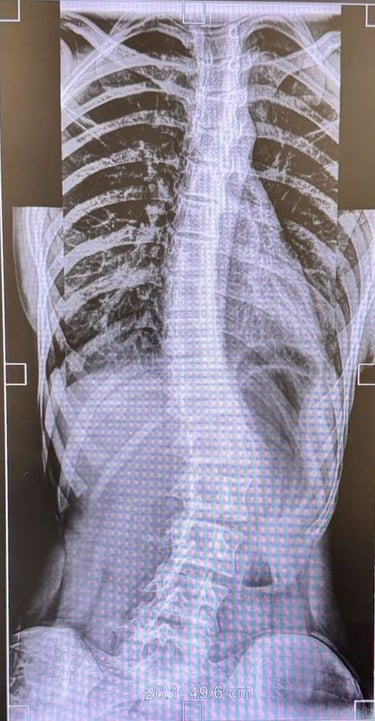

Comprehensive evaluation and surgical correction of scoliosis, kyphosis, and post-infective or traumatic deformities.

Using 3-D planning and intra-operative neuromonitoring, Dr. Sivaraj achieves precise alignment and improved posture while maintaining spinal balance.

Special Expertise:

Adolescent idiopathic scoliosis

Chiari-related and congenital scoliosis

Post-tubercular kyphosis

Scoliosis & Spinal Deformity Correction